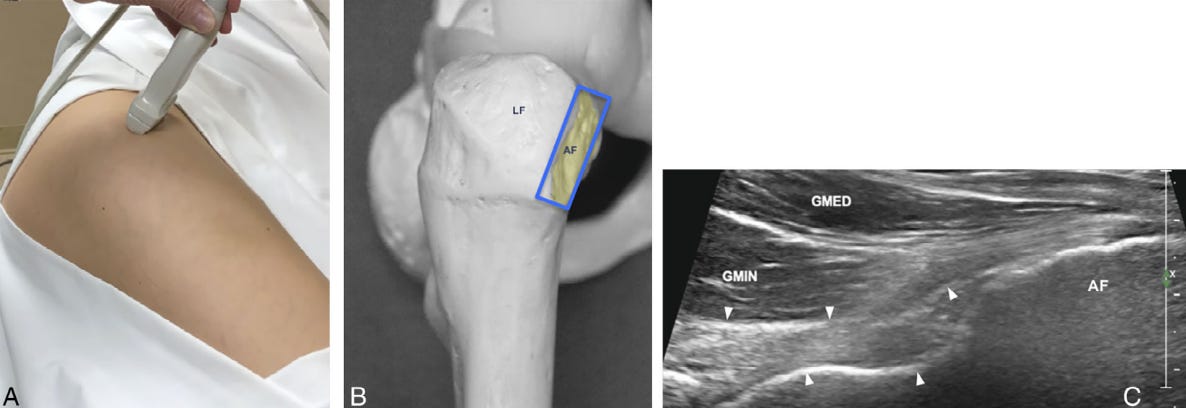

Posición del transductor e imagen en eje largo (LAX) del tendón del glúteo menor (GMIN).

A. El paciente se coloca en decúbito lateral, con la cadera ligeramente flexionada. La sonda se orienta de forma paralela a la faceta anterior tanto en ambos cortes.

B. Modelo anatómico de la cadera que muestra la faceta anterior, la orientación y la posición del transductor (rectángulo azul) en relación con la faceta anterior (AF) para obtener una imagen en eje largo del tendón del GMIN.

C. Imagen ecográfica en eje largo de la unidad músculo-tendinosa del GMIN, que muestra el músculo glúteo menor, la unión miotendinosa y la inserción del tendón del GMIN en la faceta anterior. Nótese la cápsula anterior de la cadera subyacente (puntas de flecha) y el músculo glúteo medio (GMED) situado superficialmente.